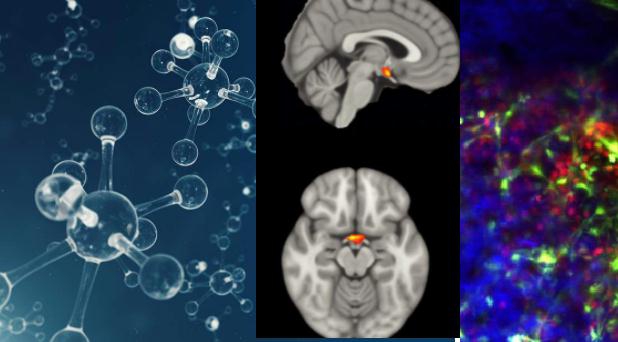

בדיקות נוספות העלו כי נשים אלה לא רק טובות יותר בזיהוי הריח של בן הזוג שלהן, אלא שהן תופסות ריח גוף של גברים באופן שונה מהנשים בקבוצת הביקורת. כאשר התבקשו לדרג את ריחות הגוף של גברים על-פי מדדים שונים, ממדדים סטנדרטיים של נעימות ועוצמה ועד משתנים כגון משיכה מינית או מידת הפוריות, הנשים שסבלו מהפלות חוזרות היו ייחודיות באופן שתיארו ודירגו את הריחות, ותפיסת הריח שלהן הייתה שונה באופן משמעותי מקבוצת הביקורת. יתירה מכך, בסריקות MRI שנערכו לנשים אלה התגלה כי פקעות ההרחה שלהן – התחנה הראשונה במסלול העצבי מהאף למוח קטנות יותר בממוצע. בנוסף, סריקות fMRI, הראו תגובה מוגברת לריחות גופם של גברים בהיפותלמוס שלהן, האזור המוחי האחראי על ויסות הורמונלי, ובכלל זאת גם במהלך ההריון, אשר ממלא תפקיד מפתח באפקט ברוס במכרסמים.